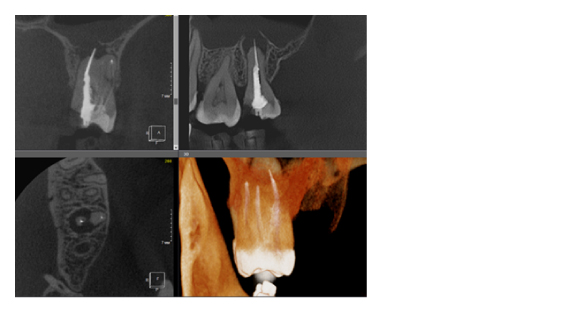

Когда мы отправляем пациента на проведение рентгенологического исследования, то подвергаем его определенному риску. Именно это нужно осознавать, так как в радиологии нет минимально безопасной дозы, поэтому любое назначение должно быть обоснованным. В связи с этим поле обзора является достаточно принципиальным параметром. Если вы врач-терапевт, занимающийся эндодонтией или ортопед, который решил оценить состояние зубов перед протезированием, то вы должны понимать, что проведение исследования с полем обзора 10x10 см будет гораздо информативнее нежели большие снимки (18x16 см и выше). В первую очередь это связано с размером вокселя, о нём я напишу чуть ниже, а второе это то, что вам придется увеличивать изображение по каждому корневому каналу, и от этого вы будете терять в качестве снимка (рис. 1). И ситуация наоборот, если вы ортодонт, то чтобы использовать весь диагностический потенциал, а также возможность загрузить данные для расчёта 3D цефалометрии, то вам нужны снимки, захватывающие весь лицевой отдел черепа. Таким образом, дентальный томограф должен обладать возможностью проведения исследований с разным FOV, обеспечивая нужды всех специалистов. Если ваша клиника базируется на терапевтическом, хирургическом и ортопедическом приёме, то на мой взгляд, можно рассмотреть дентальные томографы с полем обзора 10x10 см или 16x10 см. Последний больше актуален для тех, кто работает с ВНЧС, так как антропометрически в 16 см даже у брахицефалов сустав должен попадать. Если в клинике есть ортодонтическое направление, функциональная стоматология, ЛОР-практика или ЧЛХ, то, безусловно, вышепредставленные снимки не будут отражать всех данных, которые необходимы для диагностики и планирования лечения. Здесь лучше рассмотреть конусно-лучевые компьютерные томографы с зоной сканирования 18x16 или 20x20 см. Особо стоит отметить понятие «сшивки». Есть дентальные томографы, которые делают один цельный снимок размерами, которые описаны выше, а есть аппараты, которым нужно провести две экспозиции и сшить изображения вместе, чтобы получился необходимый объём исследования. Как правило, вторые томографы чуть дешевле, но всё зависит от того, насколько вам нужна максимальная точность исследования. Если при сшивке челюсти и зубы, как правило, совмещаются практически идеально, то на уровне позвоночного столба происходит наслоение тканей и от него уже не избавиться (рис. 2). Второй отрицательный момент – это износ оборудования, логично, что он будет быстрее, так что экономия средств — это ещё спорный вопрос.

Рис. 1. Представлены два исследования (10x10 см и 20x20 см). На обоих изображениях хорошо видна канально-корневая система зубов, но, если масштабировать второе исследование, то качество неминуемо снизится, как и диагностическая эндодонтическая эффективность.